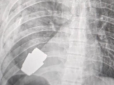

Могла здетонувати у будь-який момент: Лікарі видалили нерозірвану гранату з тіла військового (фото)

Військові лікарі провели операцію з видалення гранати ВОГ, яка не розірвалася, з тіла військовослужбовця. Боєприпас діставали у присутності двох саперів, які страхували безпеку медичного персоналу. Про це розповіла заступниця міністра оборони України ...